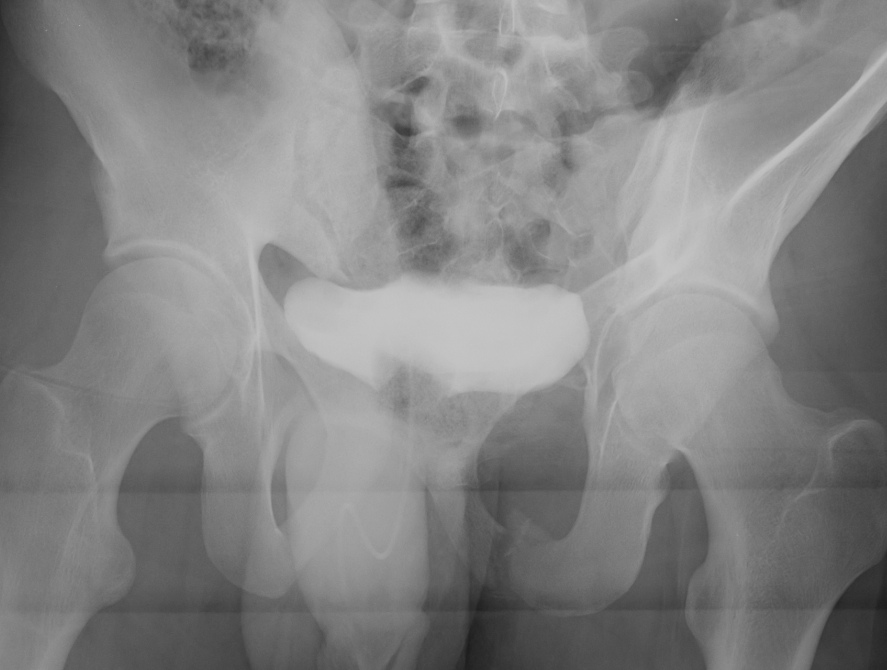

APC-1

Pelvic Fracture APC 2

< 2.5 cm diastasis with no anterior SI joint widening

APC-2

Pelvic Fracture APC 2Pelvis APC 2

Pubic diastasis with anterior SI joint widening on the right